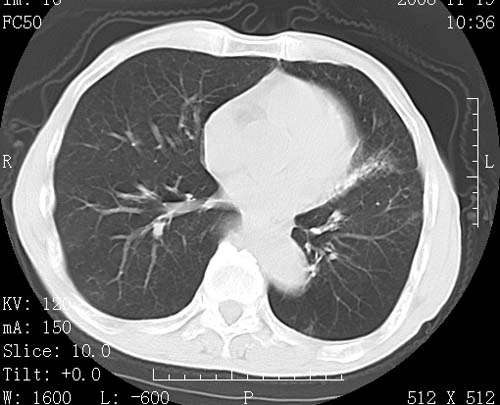

标题: CT16691:m 67 胃镜确诊食管下段及贲门癌 [打印本页]

标题: CT16691:m 67 胃镜确诊食管下段及贲门癌

术前查体,双肺部结节是转移?结核?请点评

1)符合食管癌表现。2)两肺及纵隔淋巴结多发性转移瘤。3)左肺上叶舌段及两肺下叶炎症感染。

食管癌伴双肺转移,评述:肺部毛细血管网丰富,全身血液均快速流经肺部,癌细胞容易过滤定植,形成转移瘤,影象特点为以毛细血管末梢为中心的结节灶,边缘光滑锐利,少见有中心空洞着,不同来源的转移瘤可有各自特点,如甲状腺癌为双肺弥漫性微结节,本例有原发灶,双肺影象灶典型,左肺舌段条带状网格样伴胸膜天幕征,可视为癌性淋巴管炎。

左肺舌段有斑点钙化灶,能否说明是结核而不是转移?如果是转移将放弃手术改成化疗,如果是结核将考虑择期手术